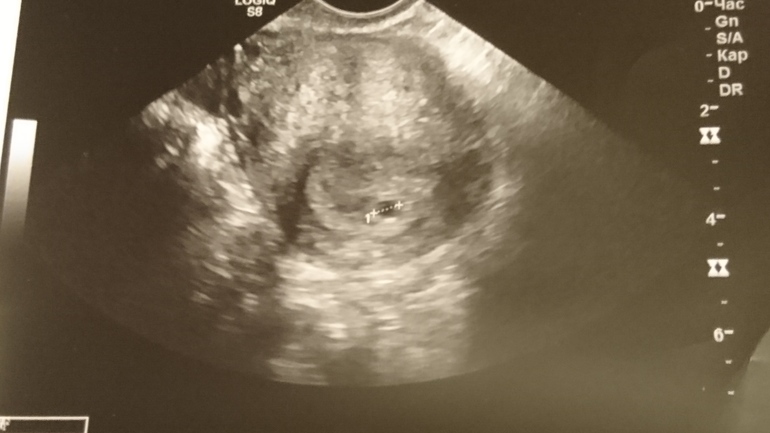

Боли у вас скорее всего от жёлтого тела на яичнике. А по поводу центра матки вообще бред. Матка см 4. У неё по кругу везде стенки :) Она как полый шарик. Пя прикрепляется к стенке в любом месте, где ему понравится. Вот мое первое узи :) вообщем то все тоже в цетре, но все где надо :)

Вы знаете, у меня тоже обе первые фотки в таком же виде! Все у вас нормально. Правильно Вам многие говорят, через пару недель сходите к другому узисту, сделайте снимок и результаты и тому тыкнете в лицо и жалобу накатайте, чтоб такие недоросли не работали в таких местах!